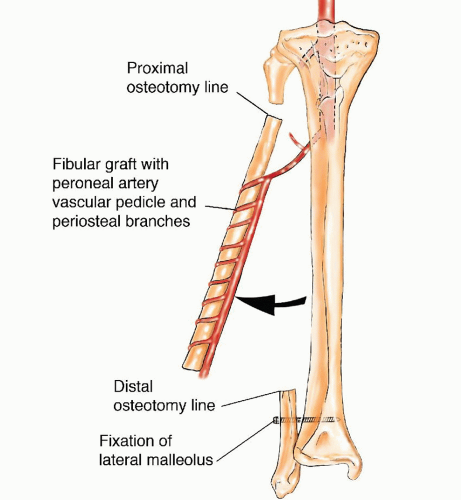

Free Vascularized Fibular Grafting—25 Years’ Experience: Tips …

Vascularized fibula bone graft to reconstruct bone defect in the …

Free Fibular Flap | Musculoskeletal Key

The Use of Free Vascularized Fibular Grafts for Reconstruction of …

The Use of Free Vascularized Fibular Grafts for Reconstruction of …